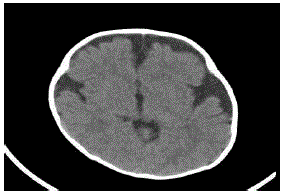

Lactente de sete meses de idade está em consulta de rotina de puericultura. A mãe teve uma gestação e parto sem intercorrências e nasceu com um perímetro cefálico de 35 cm. Ao exame neurológico, foi evidenciada uma fontanela ampla e depressível, perímetro cefálico de 48 cm, com marcos do desenvolvimento normais.

Na investigação, foi realizada tomografia computadorizada de crânio (ver abaixo).